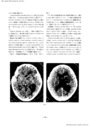

第3脳室近傍腫瘍の神経放射線診断-脳血管撮影を中心に- III 主に第3脳室の側方に発育する腫瘍(1)